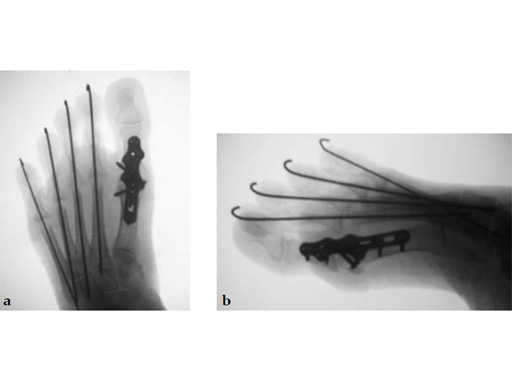

Case 1: First MP fusion VA-LCP

A 57-year-old woman has suffered rheumatoid arthritis for several years. She presented with pain and deformity in the left forefoot moreso than in the right. Clinical examination reveals severe hallux valgus deformity and dislocation of MP joints 11 through V, with synovitis.

Case provided by Juan Bernardo Gerstner, Cali, Columbia

A dorsal transtendinous approach was used and reaming of the first MT head and basal articular surface of the proximal phalanx was performed with the new reamers (see Fig. 3a-b).

A left MP fusion was performed as well as a II to V MT head resection arthroplasty, and fixed with K-wires for 4 weeks (see Fig. 4a-b). The patient was weight bearing immediately with wooden shoes and K-wires were removed 4 weeks postoperatively.